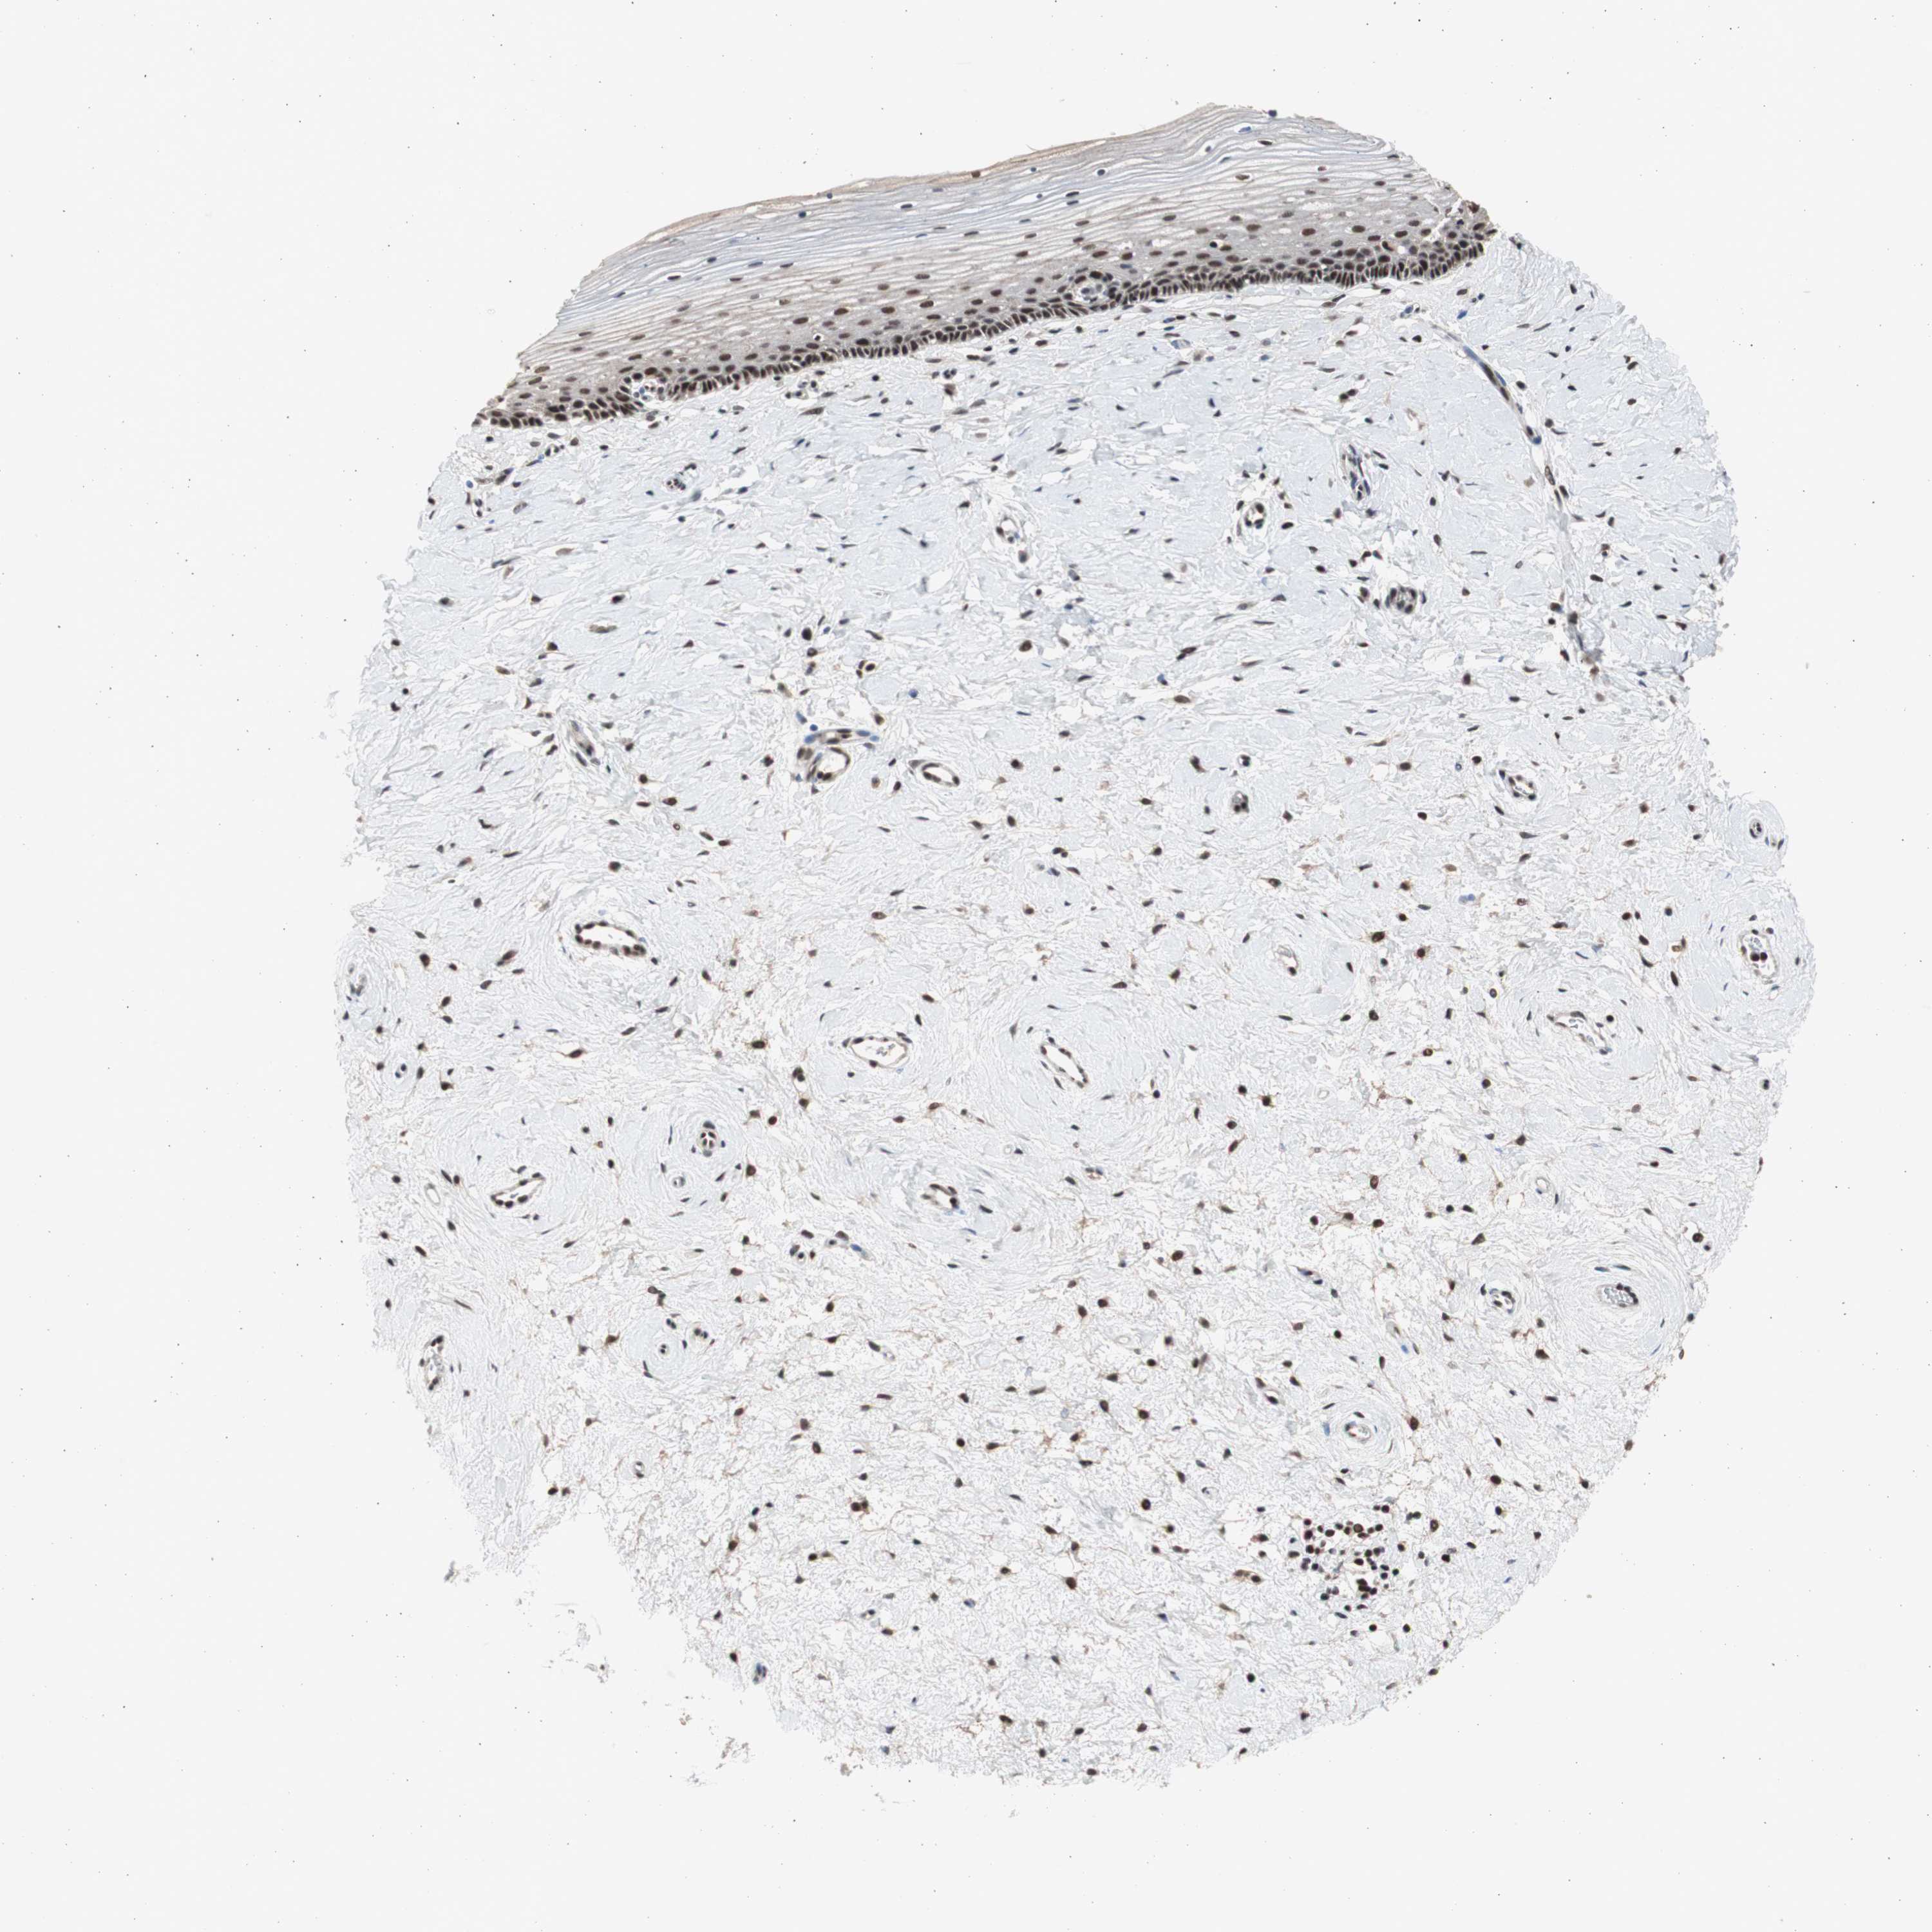

CERVIX - Antibody stainingi

Antibody staining in the annotated cell types in the current human tissue is reported as not detected, low, medium, or high, based on conventional immunohistochemistry profiling in selected tissues. This score is based on the combination of the staining intensity and fraction of stained cells.

Each image is clickable and will lead to virtual microscopy that enables deeper exploration of all samples and also displays staining intensity scores, fraction scores and subcellular localization as well as patient and tissue information for each sample.

Antibody HPA006914Antibody CAB004563

Glandular cells HighLow

Squamous epithelial cells HighHigh